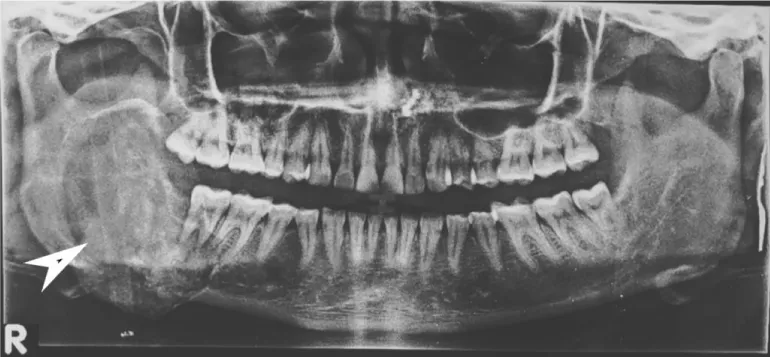

Orthopantomography (OPG) showed a large well-defined mixed density predominantly radiolucent lesion measuring 5.8 x 4.5 cm involving the ramus and body of right hemi-mandible causing their significant expansion reaching up to the root of the right lower molar tooth with no definite evidence of a cortical break. There was no evidence of dislocation, destruction, or erosion of the molar tooth. Few faint ill-defined radio-opaque areas were seen within the lesion representing intra-lesional calcific foci/ cementing material. This was reported as a Fibro-osseous lesion or ameloblastoma (Figure 3).

In the Radiological aspect, initially, the cemento-ossifying fibroma appears as a well-defined radiolucent lesion with no evidence of internal radio densities. As the tumor progresses, there is evidence of calcification so that the radiolucent area opacifies, and eventually, the lesion appears as a lobulated almost complete radiopaque mass in the mature stage. An important diagnostic feature of cemento-ossifying fibroma is the expansion of lesions equally in all directions and present as a round tumor mass. The cortical plate may be expanded, displaced, thinned out, and remains intact. Teeth adjacent to or involved in the lesion may be displaced but resorption is not associated with this tumor [3,4,6,9]. In our case the tumor was large well corticated, sharply marginated mixed density with high densities representing calcific foci/cementing material, expansile lesion with no evidence of bone destruction or cortical break.